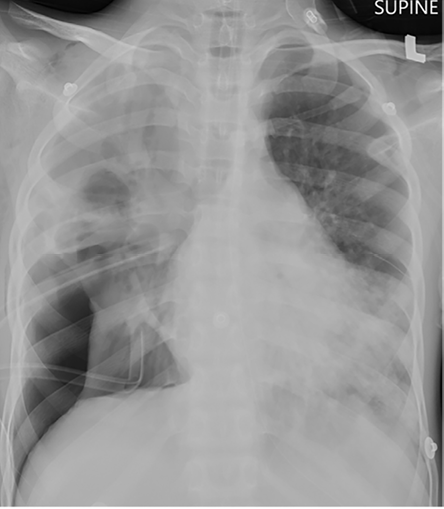

Bedside ultrasound revealed a right-sided multiseptated collection. Thoracocentesis yielded purulent fluid, prompting the placement of a chest drain [Figure 2]. Pleural fluid analysis revealed a protein level of 16 g/L and a lactate dehydrogenase level of 5355 u/L. Due to the need for high-ventilator settings and persistent bubbling from the chest

drain, a bronchopulmonary fistula was suspected, leading to the insertion of a second chest tube to optimize ventilation. Informed consent was obtained from the patient’s father.

Figure 2: Chest X-Ray on 3 August 2022. The frontal radiograph, obtained post-intubation, reveals lucency along the lower zone of the right hemithorax consistent with pneumothorax, resulting in compression of the adjacent lungsgarette or vaping product use-associated lung injury.